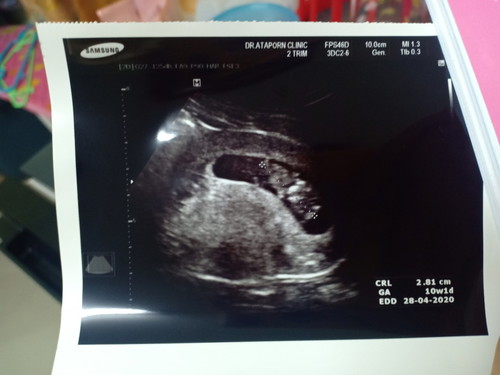

เพิ่งไปฝากครรภ์มาคะ ตอนนี้ได้10week2day หัวใจน้องเต้นปกติ 2.81 ซม. อยากทราบว่าปกติไหมคะ พอดีคุณแม่เป็นคนน้ำหนักน้อย ตอนนี้น้ำหนักก็ยังเท่าเดิม แพ้ท้องหนักมาก กินข้าวได้นิดเดียว กังวลมากเลยคะ กลัวน้องไม่แข็งแรง